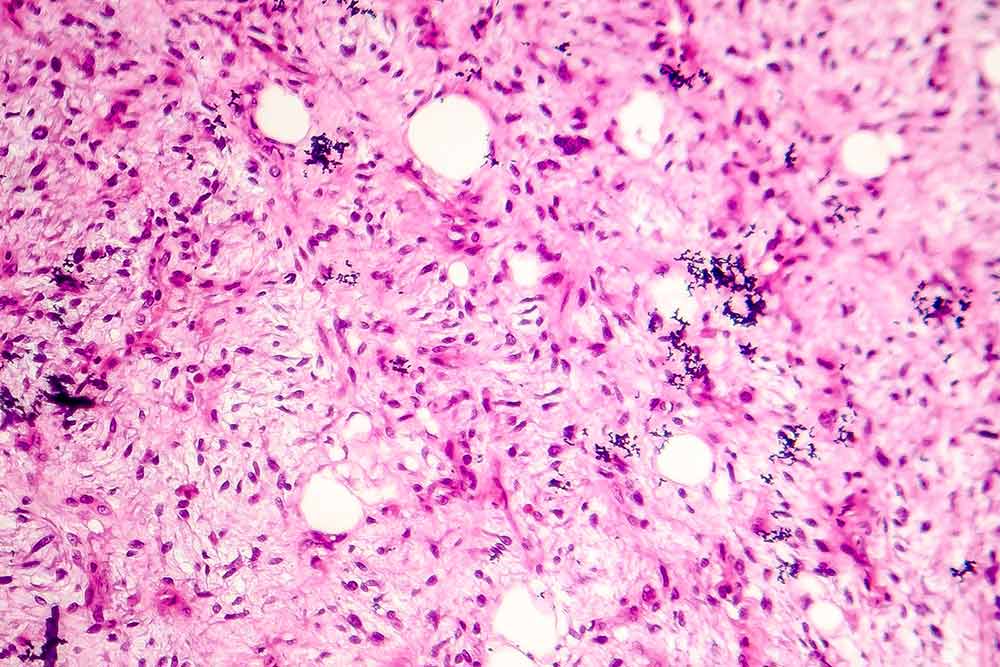

Image of a liposarcoma, soft tissue sarcoma, under a microscope.